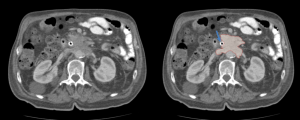

EXTRA-MEDULLARY HEMATOPOIESIS (EMH)

EMH is often incidental and represents compensatory blood cell production outside the bone marrow as a compensatory mechanism for [10]:

- Decreased bone marrow hematopoiesis or increased peripheral destruction of blood cells.

- Secondary to bone marrow infiltration.

Although most cases present microscopically with homogeneous hepatosplenomegaly, macroscopic EMH may appear at several sites, including the thorax (most commonly as paraspinal masses), liver and spleen, and retroperitoneum, where it commonly appear as unilateral or bilateral soft-tissue masses, frequently involving the perinephric space [11]. These lesions typically form a soft-tissue rind without renal mass effect, with foci of fat-attenuation may be interspersed within the regions of soft tissue, and are hypovascular on post-contrast imaging. Calcifications are uncommon.

The characteristic perinephric distribution generally distinguishes EMH from retroperitoneal fibrosis, though differentiation becomes difficult when RPF exhibits atypical peri-renal extension. Supporting features such as hepatosplenomegaly or skeletal abnormalities related to the underlying haematological disorder (e.g., sclerotic bone in myelofibrosis or “H-shaped” vertebrae in sickle-cell disease) aid in establishing the correct diagnosis.

Depending on the phase, we will observe different radiological characteristics: